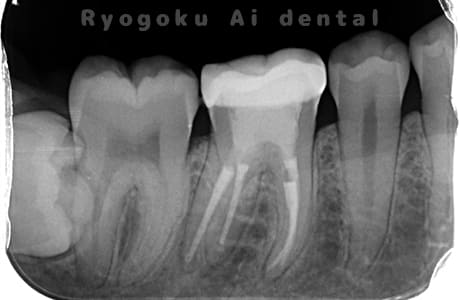

Case02

-

- 原因

- 慢性根尖性歯周炎

- 治療期間

- 3ヶ月

- 治療内容

- マイクロエンド

- 治療費用

- 121,000円

噛むと痛みが出る、とのことで来院した患者様です。他院での根管治療を終えてましたが、根尖病変を認めるため、マイクロエンドを行いました。